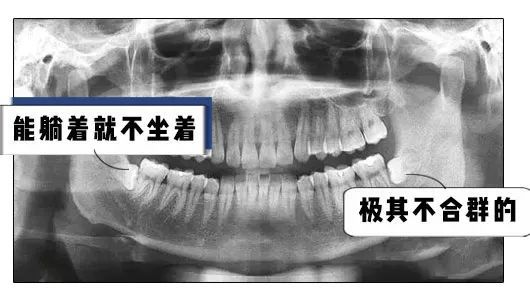

大部分人智齿都这样长

各种奇形怪状